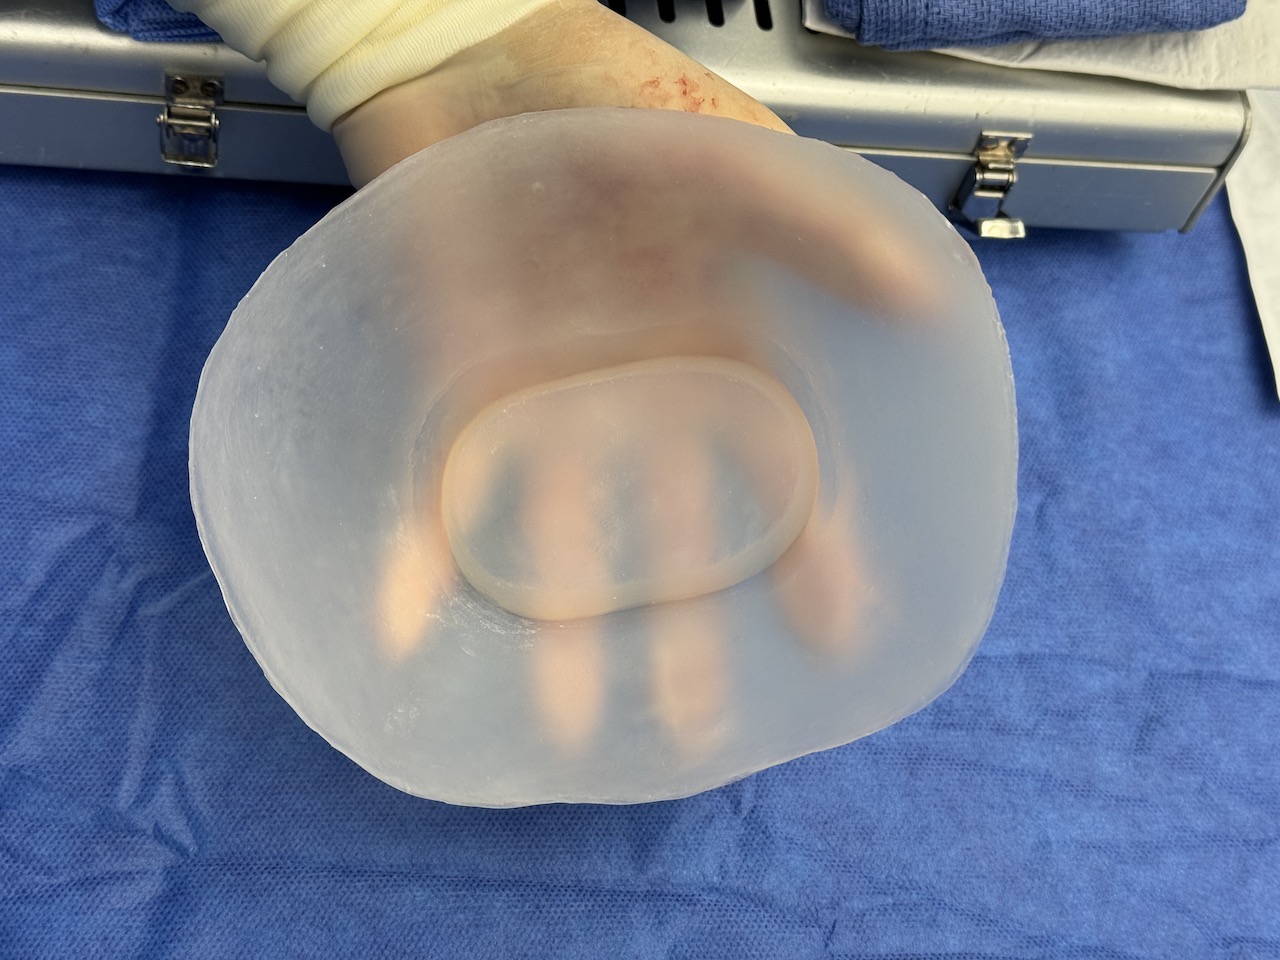

Severe narrowing skull deformity from prior sagittal craniosynostosis repair as an adult.

Complete replacement of entire skull by a custom implant with temporal fat injections.

Severe narrowing skull deformity from prior sagittal craniosynostosis repair as an adult.

Complete replacement of entire skull by a custom implant with temporal fat injections.